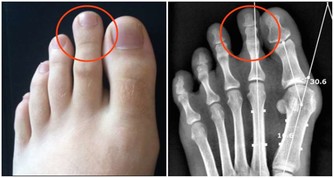

第一次手術我的左側甲狀旁腺就被拿掉了,但是我不知道,醫生也沒有醫囑。在那個年代也沒有補鈣的概念的。我記得大肆廣告補鈣是在95、96年,我87年做的手術時可沒人給我說過這個事情。幸好我右側的甲狀旁腺保留了,它的功能也有了代償。所以沒有發生過抽搐等現象。但是其實身體是出於缺鈣的症狀的,我的腳趾甲就沒長起來,只有兩個大腳趾有指甲。

萬幸我的個子是長起來了,165cm,算是中等個了。由於無知,上大學時偷偷停了半年的藥,我就是不想終生服藥,想看看停藥有什麼不行的。半年後,甲減的症狀越來越明顯了,出現了思維跟不上的情況,明顯反應遲鈍。更壞的結果很快就來了,在一次體育跳遠課上輕輕的一跳,就跳成了左腿脛骨粉碎性骨折,打了一個月石膏。後來經過一年的康復鍛煉,腿才又恢復了。我從骨折後有開始恢復服甲狀腺素片了。甲狀腺癌復發有可能是從那時開始的。

在去年的第二次手術,做右側甲狀腺摘除時就把甲狀旁腺也摘除了。這下我的身體就一點甲狀旁腺都沒有了。它的反應非常明顯,而且迅速。手術當晚就因血鈣的迅速流失,腰椎疼了一晚上,直到第二天早上醫生查房後,給我靜脈注射了葡萄糖酸鈣,才止住了疼。

別人一輩子的針都被我紮了。但是沒完,醫生還讓我今後一定定期監測血鈣的含量。同時,每年應該做一次骨密度的片子,看看骨頭里鈣沉積的情況。

如果你也做了甲狀腺癌清掃術,就開始終生補鈣吧,定期監測血鈣含量,別把自己變成個玻璃人。還有一些個別的手術後遺症就屬於手術事故了。那就另當別論了。